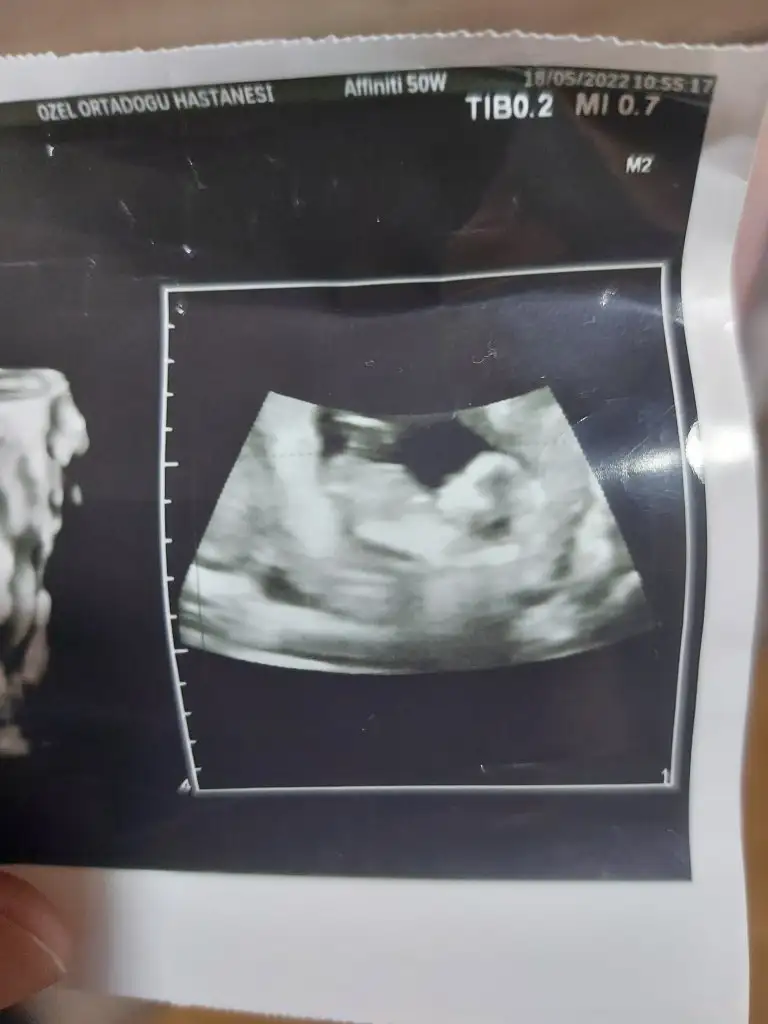

5 ve 14. haftaya kadar olan ultrason fotolarınızı paylaşın. Vajinadan mı yoksa karından mı çekildiğini ve kaç haftalık olduğunu da mutlaka belirtin.

Erkek görünüyorMerhaba bana da tahminde bulunabilir misinizkarından usgEki Görüntüle 3073103

Kız görünüyor tabiki en iyi 11 12 13 haftalarmerhaba banada tahminde bulunabilirmisiniz rica etsem.